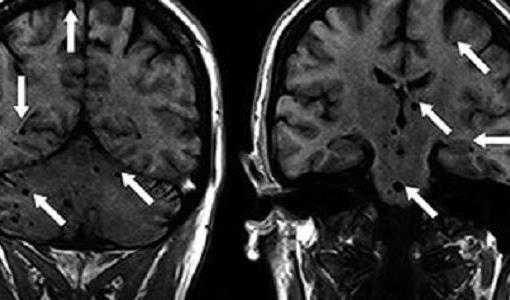

- МРТ головного мозга — при парагонимозе выявляются кальцификаты, похожие на мыльные пузыри.

Различают острое и хроническое поражение головного мозга. Для острого характерно внезапное развитие неврологической симптоматики, обычно на фоне легочной патологии. При хроническом нередки эпилептические припадки и стойкие неврологические нарушения; при рентгенографии черепа обнаруживают кальцификаты в виде «мыльных пузырей».

Поражение мозга

Несмотря на то, что данная форма парагонимоза встречается крайне редко, она является наиболее распространенной внелегочной формой недуга. При поражении головного мозга требуется срочная госпитализация. Ранние проявления напоминают менингоэнцефалит и длятся в течение двух месяцев. Различают острое и хроническое поражение головного мозга.

Острая форма заболевания проявляется неврологической симптоматикой, но, как правило, на фоне легочной патологии.

Симптомы хронической формы: